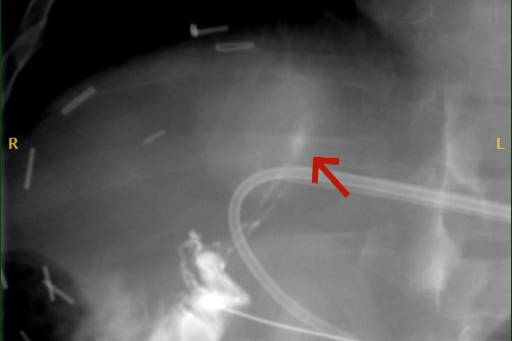

精准注入栓塞剂(重庆医科大学附属儿童医院供图)

手术的核心难点在于精准穿刺目标淋巴管。安安的肝脏淋巴管纤细、不可见,且深藏于肝实质中心,周围遍布重要血管与胆道,穿刺针需避开所有关键结构。最终,团队制定周详方案,凭借高超技术和默契配合,顺利完成手术。